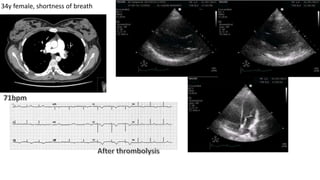

34y female, shortness of breath

BP 80/50 mmHg

Courtesy of Hatem Soliman